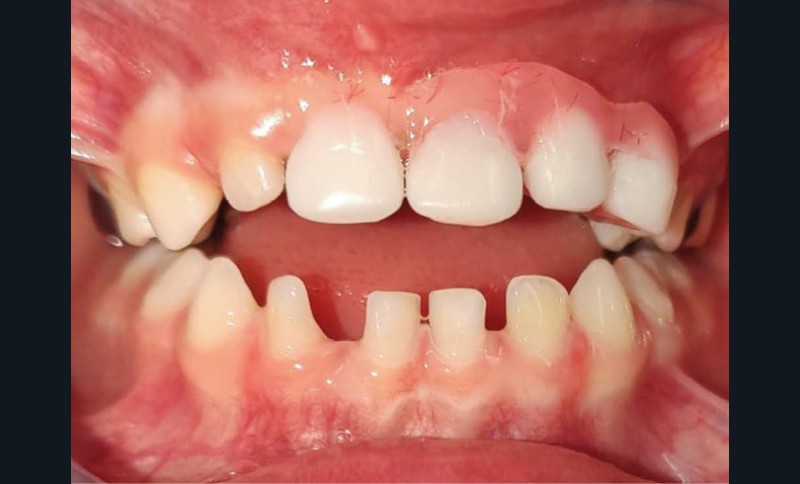

Quelles restaurations esthétiques pour la perte d’une incisive temporaire ?

Estelle Moulis : Les prothèses pédiatriques antérieures permettent de rendre le sourire aux enfants grâce à des reconstitutions esthétiques. Elles permettent de rétablir les fonctions perturbées afin de prévenir les conséquences néfastes et d’assurer une croissance harmonieuse.